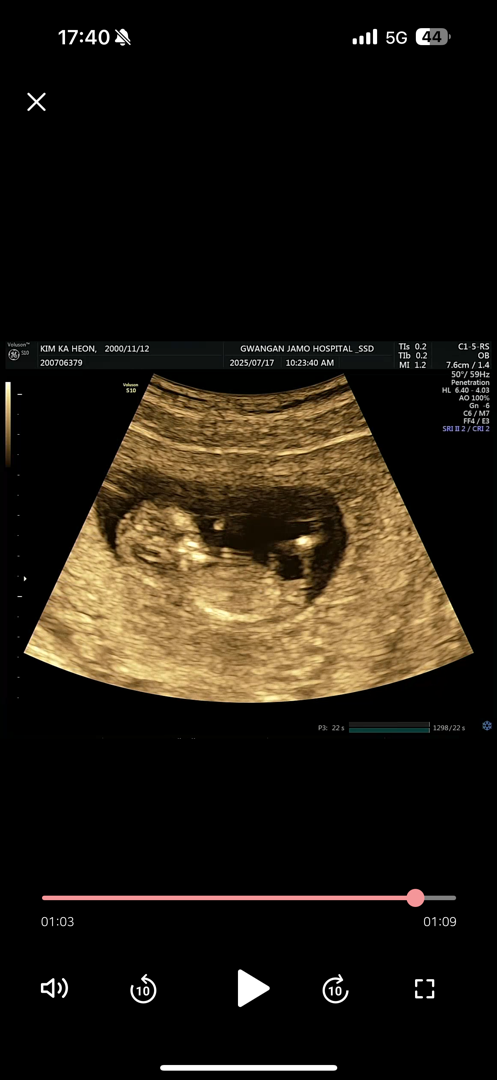

각도법이든 뭐든 성별 봐줄 전문가 뭐같이

11주6 낼이면 12주 너무 궁금한데 뭐같아?